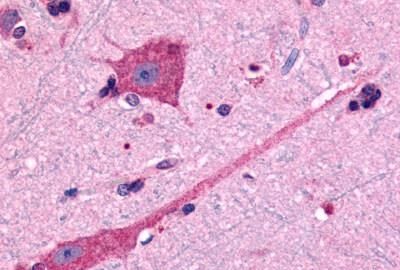

IHC-P analysis of human brain, neurons and glia tissue using GTX71747 Dopamine Receptor D2 antibody.

Antigen retrieval : Heat-induced antigen retrieval